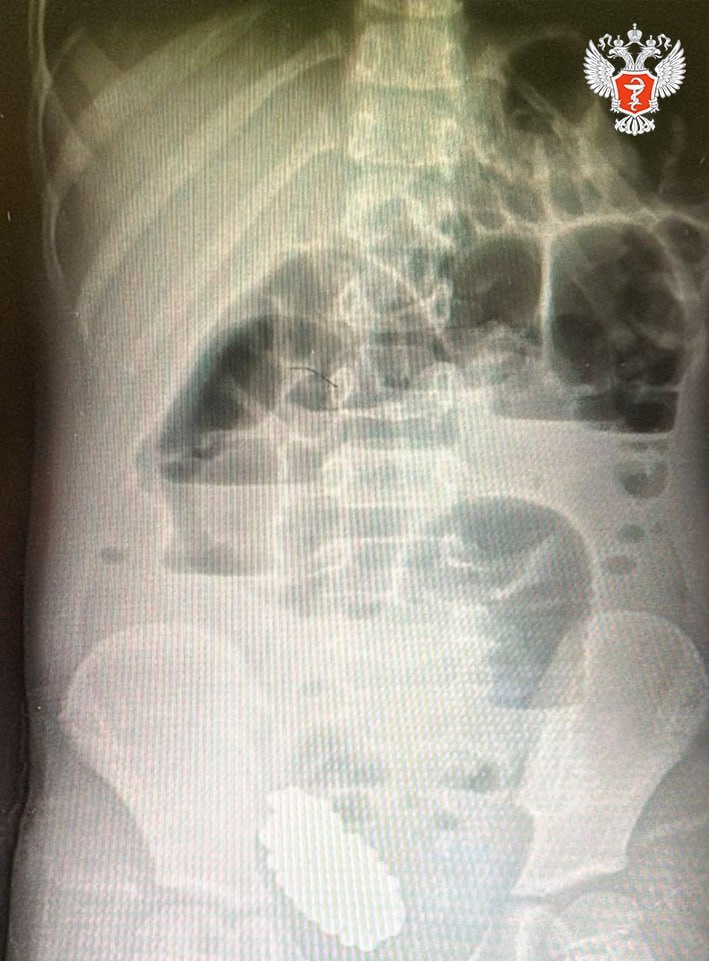

Врачи извлекли 134 магнита из кишечника 6 летней девочки в Волгограде У девочки были все признаки ОРВИ но оказалось что ситуация гораздо сложнее В августе текущего года юная жительница Волгограда проглотила 134 магнитных шарика и была экстренно доставлена на операционный стол Как сообщили в областном комитете здравоохранения девочку на скорой помощи привезли в больницу 7 с симптомами напоминающими ОРВИ У ребенка наблюдалась высокая температура и родители самостоятельно начали лечить ее от респираторной инфекции Однако улучшения состояния не происходило Через шесть дней после проглатывания магнитов состояние девочки резко ухудшилось потребовалась срочная госпитализация Медики с помощью рентгенологического исследования обнаружили кишечную непроходимость вызванную инородным телом На рентгеновском снимке четко просматривались 134 магнитных шарика которые сдавливали стенки кишечника вызывая сильные боли у пациентки Врачи выполнили лапароскопическую операцию и аккуратно извлекли все магниты из организма ребенка После проведенного хирургического вмешательства девочка чувствует себя хорошо и продолжает восстановление

Лечили от ОРВИ Волгоградские врачи спасли жизнь маленькой девочке которая проглотила 134 магнитных шарика и нуждалась в срочной медпомощи Как сообщили V102 RU в Минздраве России ребенок поступил с симптомами похожими на ОРВИ и болями в животе в больницу скорой помощи 7 Волгограда Родители девочки рассказали что у ребенка неделю назад поднялась температура Девочку стали лечить от респираторной инфекции но через 6 дней ее состояние резко ухудшилось Ребенка экстренно доставили в больницу В ходе обследования врачи выявили кишечную непроходимость вызванную инородным телом Рентген показал массивный конгломерат из 134 магнитных шариков которые сдавливали стенки кишечника рассказали в Минздраве Фото Минздрав России t me

Лечили от ОРВИ в Волгограде хирурги спасли девочку с сотней магнитных шариков в кишечнике В волгоградскую клиническую больницу скорой помощи 7 привезли девочку с симптомами похожими на ОРВИ и болями в животе Как рассказали Волжский ру в Минздраве России сначала у пациентки поднялась температура родители списали всё на респираторную инфекцию Когда через 6 дней состояние стало редко ухудшаться вызвали скорую Во время обследования выявили кишечную непроходимость из за инородного тела а на рентгене увидели массивный конгломерат из 134 магнитных шариков которые сдавливали стенки кишечника Медики успешно провели лапароскопическую операцию и аккуратно извлекли магниты В настоящее время девочка чувствует себя хорошо Подробнее на Волжский ру www volzsky ru index php wx 16 wx2 80935 ВолжскийРу волжский vlz

Волгоградским врачам удалось спасти ребенка который проглотил 134 магнитных шарика Девочка поступила с болями в животе и температурой в больницу скорой помощи 7 Дома родители лечили ее от ОРВИ однако состояние продолжало ухудшаться Через 6 дней после начала болезни ее госпитализировали На обследовании рентген показал массивный конгломерат из 134 магнитных шариков которые сдавливали стенки кишечника Специалисты успешно провели лапароскопическую операцию Сейчас маленькая пациентка чувствует себя хорошо сообщили в Минздраве РФ Подписаться Перейти на сайт